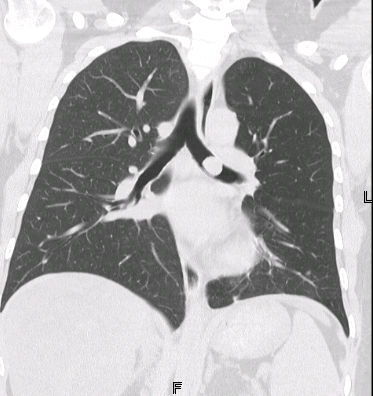

Radiology description

- Chest CT scan

- Lobulated and well circumscribed nodule implicating major bronchi

- Obstruction signs (atelectasis, bronchiectasis) can be seen (AJR Am J Roentgenol 2011;197:1073)

- Positron emission tomography (PET) scan: low to moderate uptake (mean standardized uptake value [SUV]: 3.4)

Radiology images